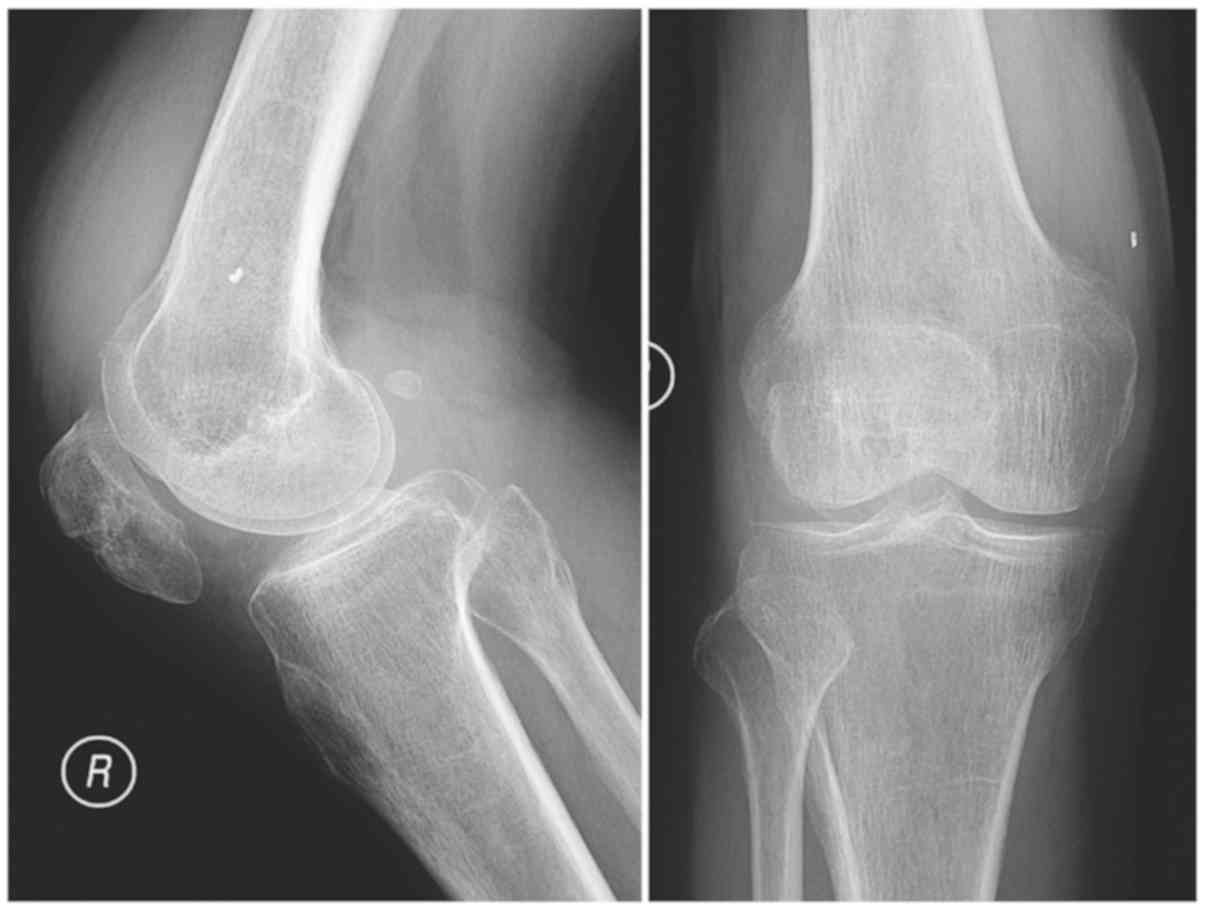

A CT scan of the lung was normal. Anterior and lateral plain images of the right knee indicated that the tibiofemoral joint space of the right knee was intact and contained a small number of osteophytes (Fig. 2). Aspiration of the right knee yielded 10 ml red, cloudy synovial fluid. No uric acid crystals were visible under a polarizing microscope. The white blood cell (WBC) count of the synovial fluid was 5895.00 106/l, with 55.4% polymorphonuclear cells. Acid-fast staining, as well as bacterial and fungal cultures, were negative, and a rapid MTB culture using the BACTEC-MGIT960 system (BD Biosciences) was negative within 2 weeks.

Figure 2.

Anterior and lateral plain images of the right knee revealing that the tibiofemoral joint space was intact and contained a small number of osteophytes.